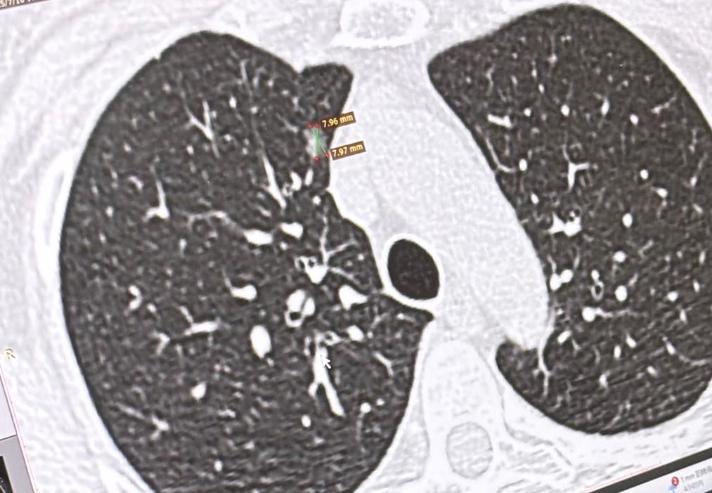

只要分期足够早,比如微浸润癌属于1A1期,浸润成分不超过5毫米,那么即使存在高危因素,手术切除后总体风险仍然很低,绝大多数患者不会出现复发或转移。

所以,当我们遇到原位癌或微浸润癌时,不必过度焦虑。从临床分期来看,原位癌是0期,微浸润癌是1A1期,尤其是它属于“微浸润”,在病理报告中常会特别标注“MI”,这和其它1A1期小于1厘米的浸润癌还有所区别。